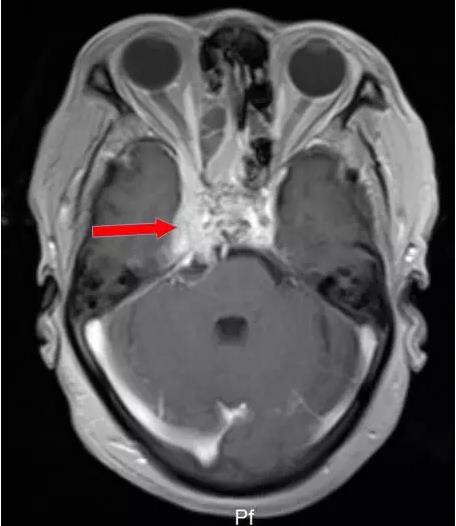

海綿竇位置影像顯示 (橫斷面),增強磁共振圖像(下圖中紅圈內高信號區即右側海綿竇)

腫瘤侵犯左側海綿竇,向后累及斜坡。